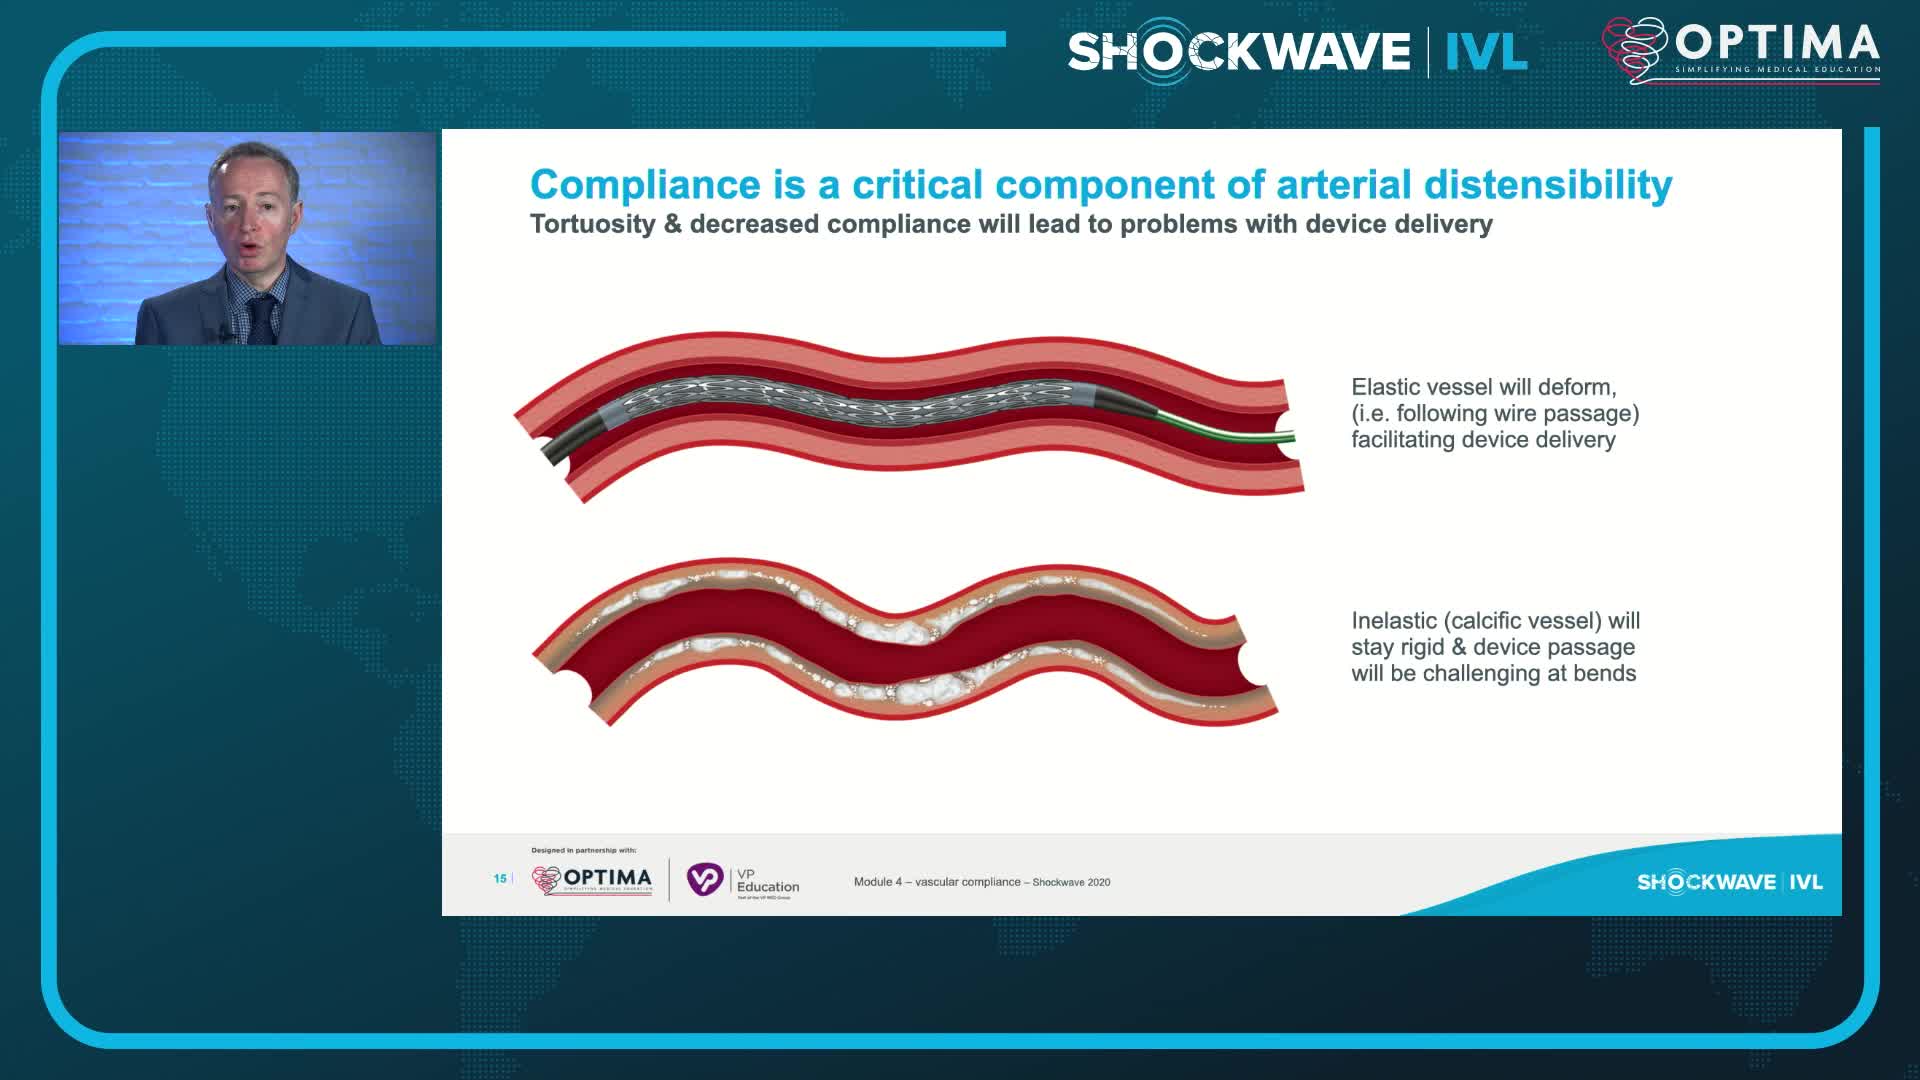

Simplify your procedures with Intravascular Lithotripsy (IVL) by safely modifying intimal and medial calcium to achieve optimal outcomes while minimising trauma, complications and costs due to its unique MOA.

IVL cracking the calcium conundrum in PAD

Peripheral IVL from the Renals to the Toes